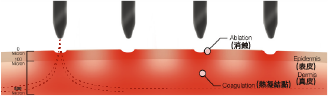

採用嶄新的納米分段式射頻及智能掃描技術,能量最高可達真皮層,從而透過熱力刺激 膠原蛋白增生。療程安全有效地重塑皮膚組織,改善各種皮膚問題,如痤瘡疤痕、深層皺紋、色素、 毛孔粗大、妊娠紋和膚色不均等。

同時產生消蝕及熱凝結點能量可穿透至皮膚500微米深度刺激膠原蛋白收縮及合成 微創傷口周邊留有完好組織,加速癒合

獨有治療模式選項,靈活控制消蝕和熱凝結比例 能量獨立傳送至每個納米電極治療後效果均勻,恢復期短